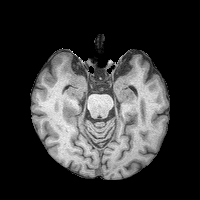

T1w(MRI)T2w(MRI)FLAIR(MRI)CTInputSynthSRBrain-IDPEPSIUNAGround TruthRefer to captionRefer to captionRefer to captionRefer to captionRefer to captionRefer to captionRefer to captionRefer to captionRefer to captionRefer to captionRefer to captionRefer to captionRefer to captionRefer to captionRefer to captionRefer to captionRefer to captionRefer to captionRefer to captionRefer to captionRefer to captionRefer to captionRefer to captionRefer to caption

Figure 3: Qualitative comparisons on healthy anatomy reconstruction, between UNA, and the state-of-the-art modality-agnostic T1w synthesis method. Testing images are generated from real healthy subjects encoded with randomly simulated pathology profiles. Pathology regions are circled in red.

Tab. 1 reports the quantitative comparison results between UNA and the state-of-the-art modality-agnostic synthesis models. UNA yields the best performance across all metrics, modalities, and regions of interest – including the full brain, healthy anatomy, and pathological regions. Remarkably, UNA outperforms competing models by a large margin in anatomy reconstruction within diseased tissue. Visualization results for each test modality are provided in Fig. 3. UNA demonstrates consistent performance across modality and resolution. Notably, other models either fail to capture any anatomy (SynthSR [26]) or generate unrealistic patterns around the pathology (Brain-ID [38] and PEPSI [39]) when given a noisy CT scan (4thth{}^{\text{th}}start_FLOATSUPERSCRIPT th end_FLOATSUPERSCRIPT row in Fig. 3), whereas UNA successfully reconstructs plausible healthy anatomy.